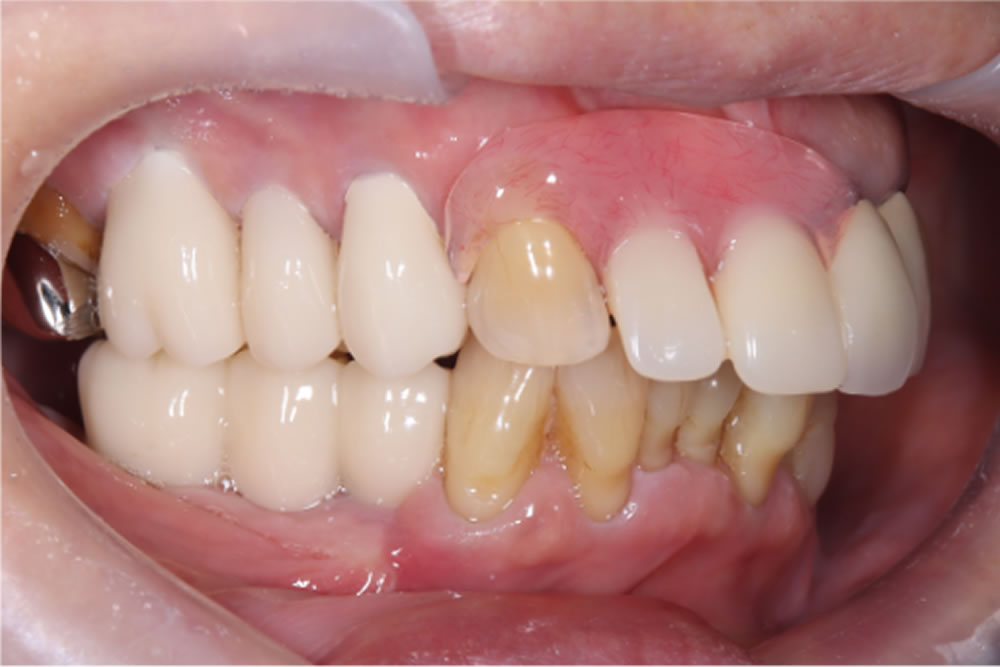

上下顎にプロビジョナル(精密仮歯)装着完了

最終的な上部構造(人工歯)を装着・治療完了

プロビジョナル(精密仮歯)での経過が問題なかったため、最終的な上部構造(人工歯)を作製・装着し、治療完了となりました。

治療前後の比較

インプラント治療により、固いものもしっかり噛めるようになったとのことでした。また、歯肉移植を併用したことで、インプラント周囲の清掃性も向上しました。